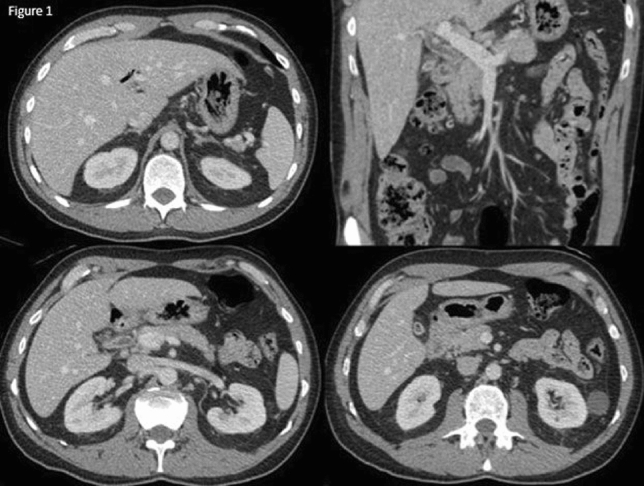

Methods: We present a 72-year-old male with prior radical cystectomy and neobladder creation complicated at the time by neobladder-cutaneous fistula and wound infection requiring revisional surgery and incisional hernia repair with mesh. He developed a large recurrent incisional hernia and underwent open hernia repair with bilateral anterior component separation, extensive lysis of adhesions, removal of prior mesh, and placement of a biologic mesh (Strattice™ RTM) in an underlay and onlay fashion. Intraoperatively, the defect measured 20 cm long by 14 cm wide. Postoperatively, he was treated for neobladder infection and CT cystogram found no extravasation from the neobladder. He presented to the emergency department 6 weeks after surgery with spontaneous partial midline wound dehiscence, with exposure of the onlay mesh and drainage of clear fluid, which was confirmed to be urine by fluid creatinine level. Repeat CT scan demonstrated a filling defect at the anterior wall of the neobladder with contrast leaking into a contained collection interposed between the anterior abdominal wall and the underlay mesh, extending superiorly between the small bowel loops and dehiscence of the midline abdominal wound. The patient was treated with a course of antibiotics and indwelling Foley catheter and bilateral nephrostomy tubes for urine diversion.

Results: Three months later, repeat CT cystogram demonstrated resolution of the leak and the nephrostomy tubes and Foley catheter were removed. The patient has continued daily wound care with significant reduction in size of the midline wound and increasing granulation tissue around the onlay mesh. He has not required further admissions to hospital and there has been no hernia recurrence so far.